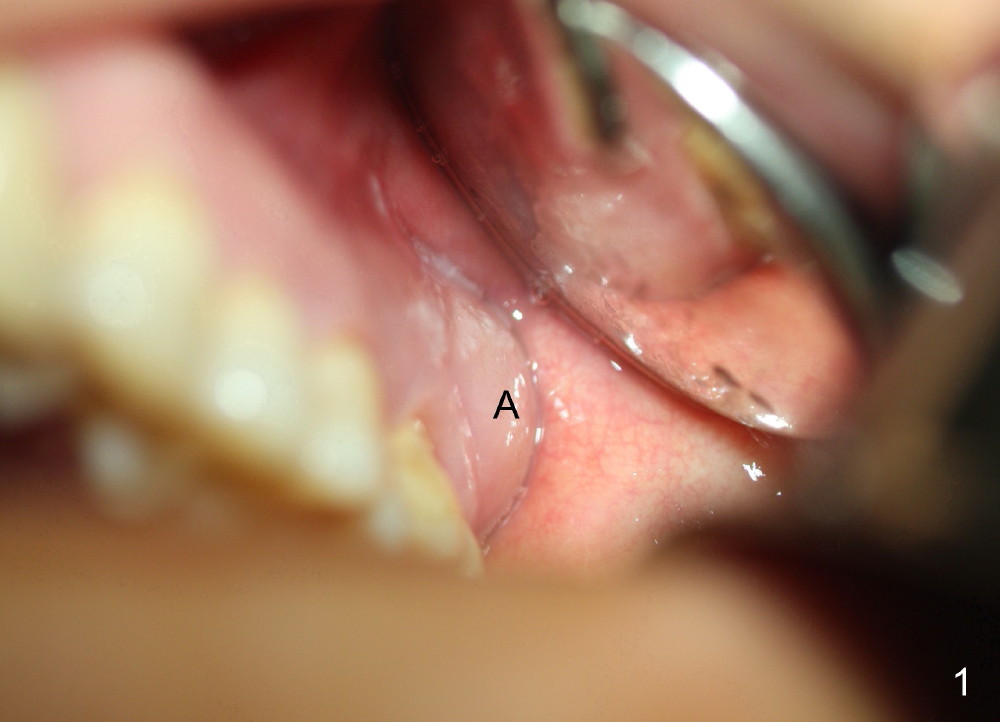

A 57-year-old lady presents for abscess buccal to the tooth #15 (Fig.1 A). Mesial and distal to the occlusal composite (Fig.2 C) is a crack line. In addition to long furcated roots, the upper border of the bone is not shown in this preop PA (arrow). Fig.3 is taken to show a thin septum surrounded by the mesiobuccal (MB), distobuccal (DB) and palatal (P) sockets (Fig.3). Osteotomy is initiated in the septum by 1.2 and 1.5 mm pilot drills, followed by 2,3,4 mm rounded tapered osteotomy at the depth of 17 mm. Nose blowing test is carried out after each step with negative result. Stability is achieved when a 4.5 mm tap is inserted at 17 mm, but the upper end of the tap is not visible (Fig.4,5). When a 5 mm tap is placed, stability is decreased, probably because the coronal end of the septum starts to break down (due to expansion). To re-gain stability, the 5 mm tap needs to go deeper. A 6 mm tap also achieves satisfactory stability at 20 mm. When the tap is removed, there is no air leakage. A 6x20 mm implant is placed with insertion torque > 60 Ncm; the upper end of the implant is still out of view in PA (Fig.6). Another problem is that the implant needs to go deeper to obtain sufficient occlusal clearance. The lower first molars and the 2nd premolars are missing. A panoramic X-ray has to be taken to show the apical end of the implant: ~ 3 mm into the sinus (Fig.7 ^). The maxillary tuberosity appears to grow downward (arrow). In other word, the tooth #15 appears to have been intruded due to overloading.